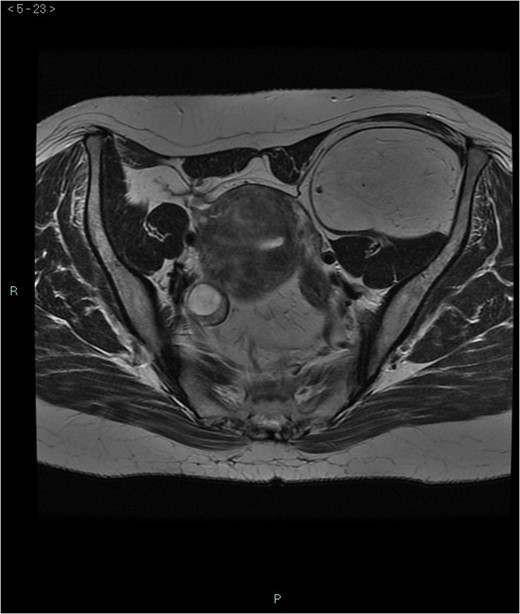

A 58-year-old woman was evaluated for lower abdominal pain, without additional symptoms. An abdominal ultrasonography revealed the presence of a 15 cm homogenous mass, located in the left pelvic cavity. Subsequent MRI showed a capsulated mass, isointense with the adipose tissue, longitudinally extending from the left inguinal area to the left leg root and located on the medial aspect of the left iliac bone. MRI also revealed within the mass some fibrotic branches containing small blood vessels. No evidence of extracapsular invasion of the surrounding structures was evident (Figs 1–6).

Preoperative differential diagnosis is mainly based on radiologic imaging and is very difficult, because no pathognomonic signs exists for diagnosis of hibernoma; usually CT-scan shows an homogenous lesion, whose density is between subcutaneous fat and skeletal muscle; MRI shows slightly lower signal intensity on T1 weighted spin-echo (T1WSE), marked enhancement and partial fat suppression on short Tau inversion recovery (STIR) and fat-saturated sequences [5].